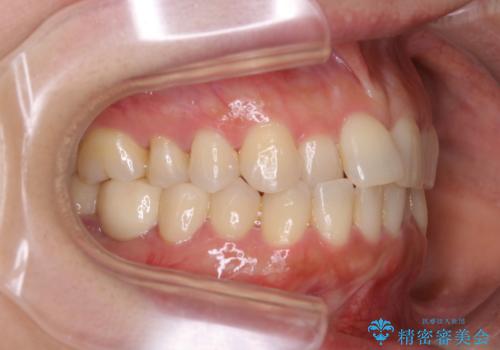

早い安いきれい!インビザラインライトで前歯のでこぼこ、反対咬合をなおす

- 前歯のがたつきと反対咬合を主訴に来院されました。

インビザライン・クリンチェック(歯のシミュレーション)を行い、

インビザラインライトで治せる範囲であることを確認し治療を開始することになりました。

今回はクリンチェックを作成したのちに、枚数が少なくても可能であることが判明したためインビザラインライトでの治療を行いました。

最初はインビザラインモデレートパッケージの予定で契約をされていたので、金額も10万円以上安くなり仕上がりも満足頂きました。